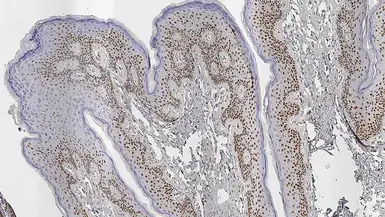

IHC-P analysis of human skin using GTX01898 Androgen Receptor antibody [AR27]. Note the nuclear staining of the epithelial cells.